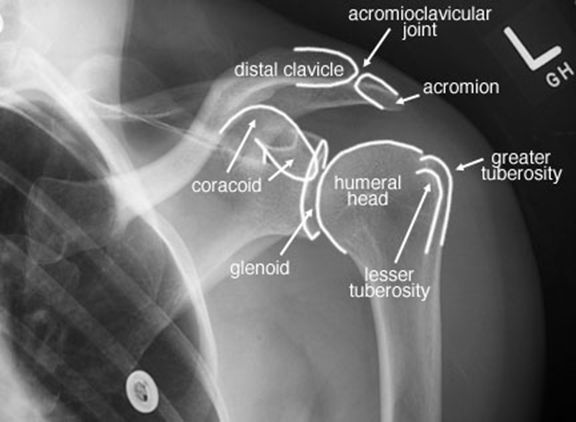

正常肩关节

肩锁关节脱位

肱骨外科颈骨折

内收或外展型损伤–最常见–骨折线为横行,伸展型损伤–间接外力引起–骨折线横行,向前成角,屈曲型损伤:较少见。